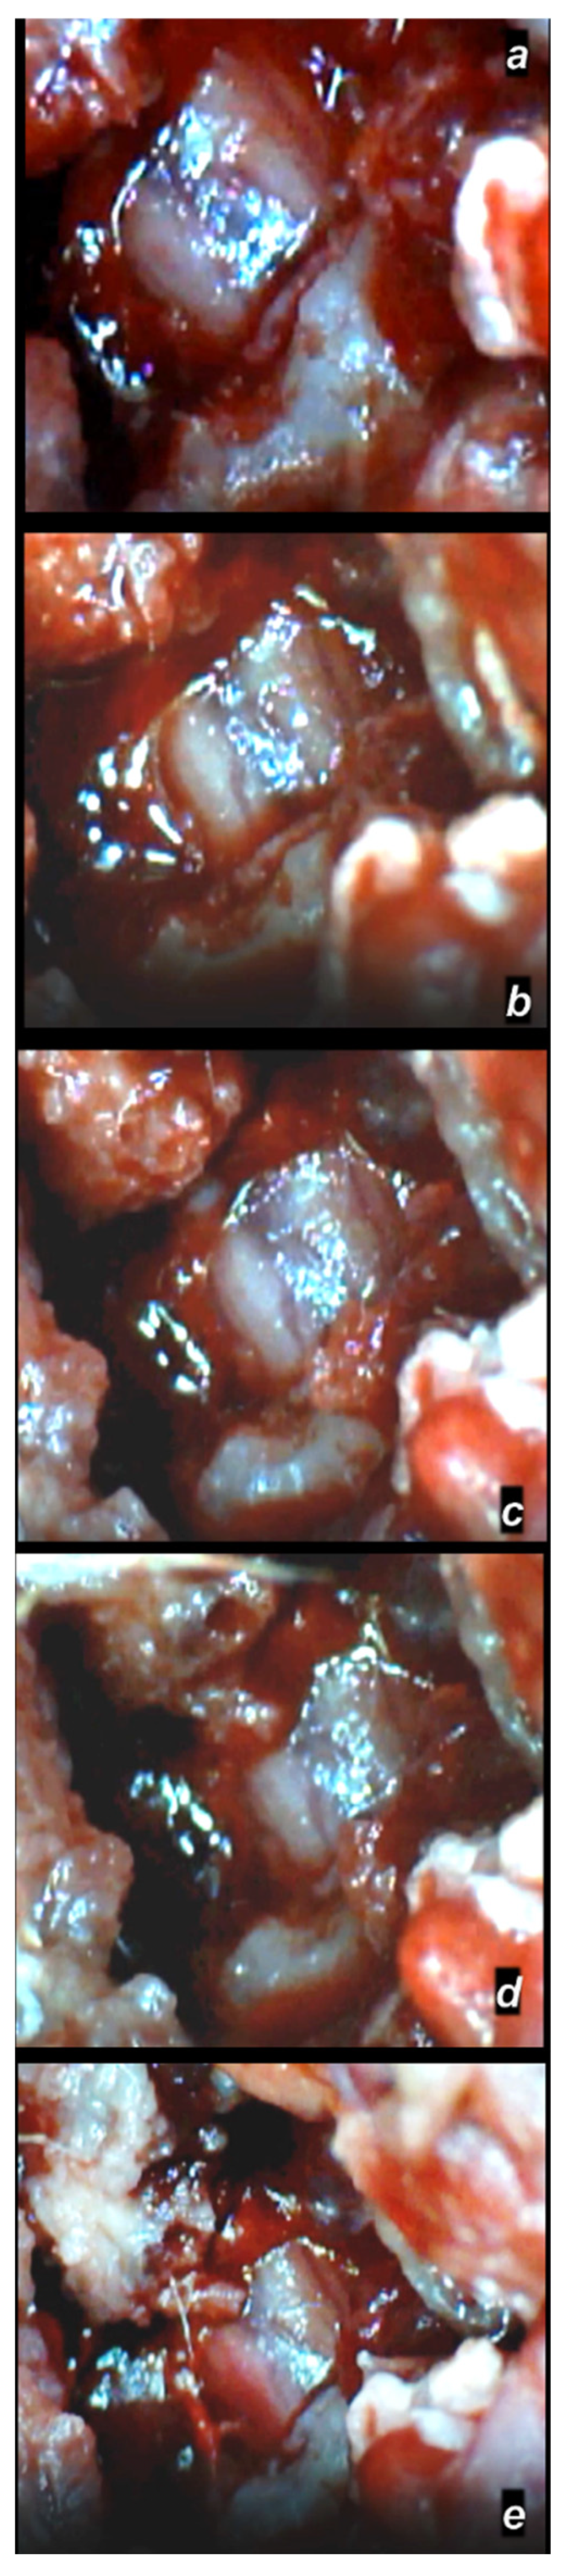

3.2. Microscopy

3.2.1. Early Post-Injury Course, Immediate Effect

3.2.2. Delayed Post-Injury Course, Immediate Effect

3.2.3. Delayed Post-Injury Course, Long-Term Effect